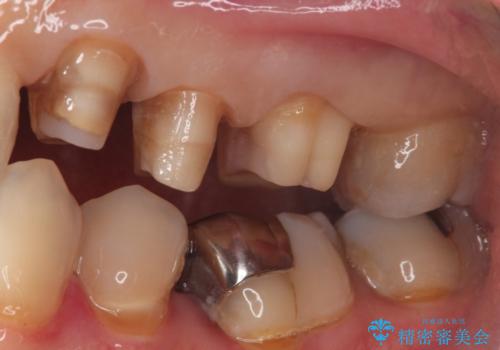

- 定期健診にて虫歯が見つかった患者さんです。県外からお越しいただいている事もあり、かなりお久しぶりの来院でした。歯と歯の間のところと銀歯の下が虫歯になっていました。被せ物はオールセラミッククラウンで治療しました。

銀歯を外すとかなり大きな虫歯になっていました。幸いぎりぎりのところで神経まで虫歯は広がっていなかったため、症状が出ない事を確認した後、オールセラミッククラウンで治療しました。虫歯除去後、残っている歯質が少なかったため、破折抵抗を考慮し部分的な被せ物ではなくクラウンを選択しました。